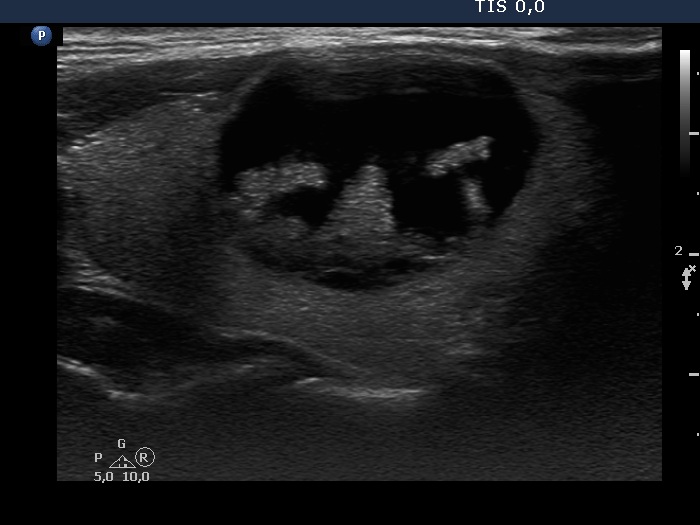

Ultrasonography. The thyroid was echonormal. The right lobe had a cystic nodule with echonormal solid components. The subtype of the cyst is difficult to define, this is probably a peripheral-type cyst.